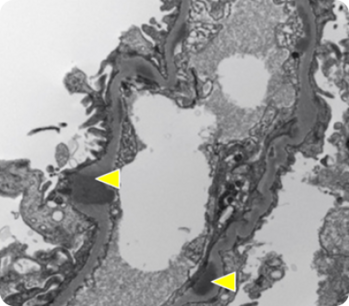

C3-гломерулопатия (C3ГП) представляет собой хроническое редкое заболевание почек, характеризующееся нарушением системы комплемента и отложением фракции C3 в биоптате почечной ткани. Это состояние включает два подтипа: болезнь плотных депозитов (БПД) и С3-гломерулонефрит (C3ГН), различающиеся по локализации отложений C3b, обнаруживаемых при электронной микроскопии.

С3ГН:

• Мезангиальные, субэндотелиальные, субэпителиальные и (или) внутримембранные отложения6—8.

• Ультраструктуральные характеристики менее выражены8.

• Наблюдается у 66% пациентов с С3ГП1.

Электронная микроскопия10

Электронная микроскопия

• Электронно-плотные отложения в мезангии вдоль ГБМ.

• Необходима электронная микроскопия для однозначного определения БПД и C3ГН1.